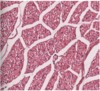

MDx

Myocyte Hypoplasia